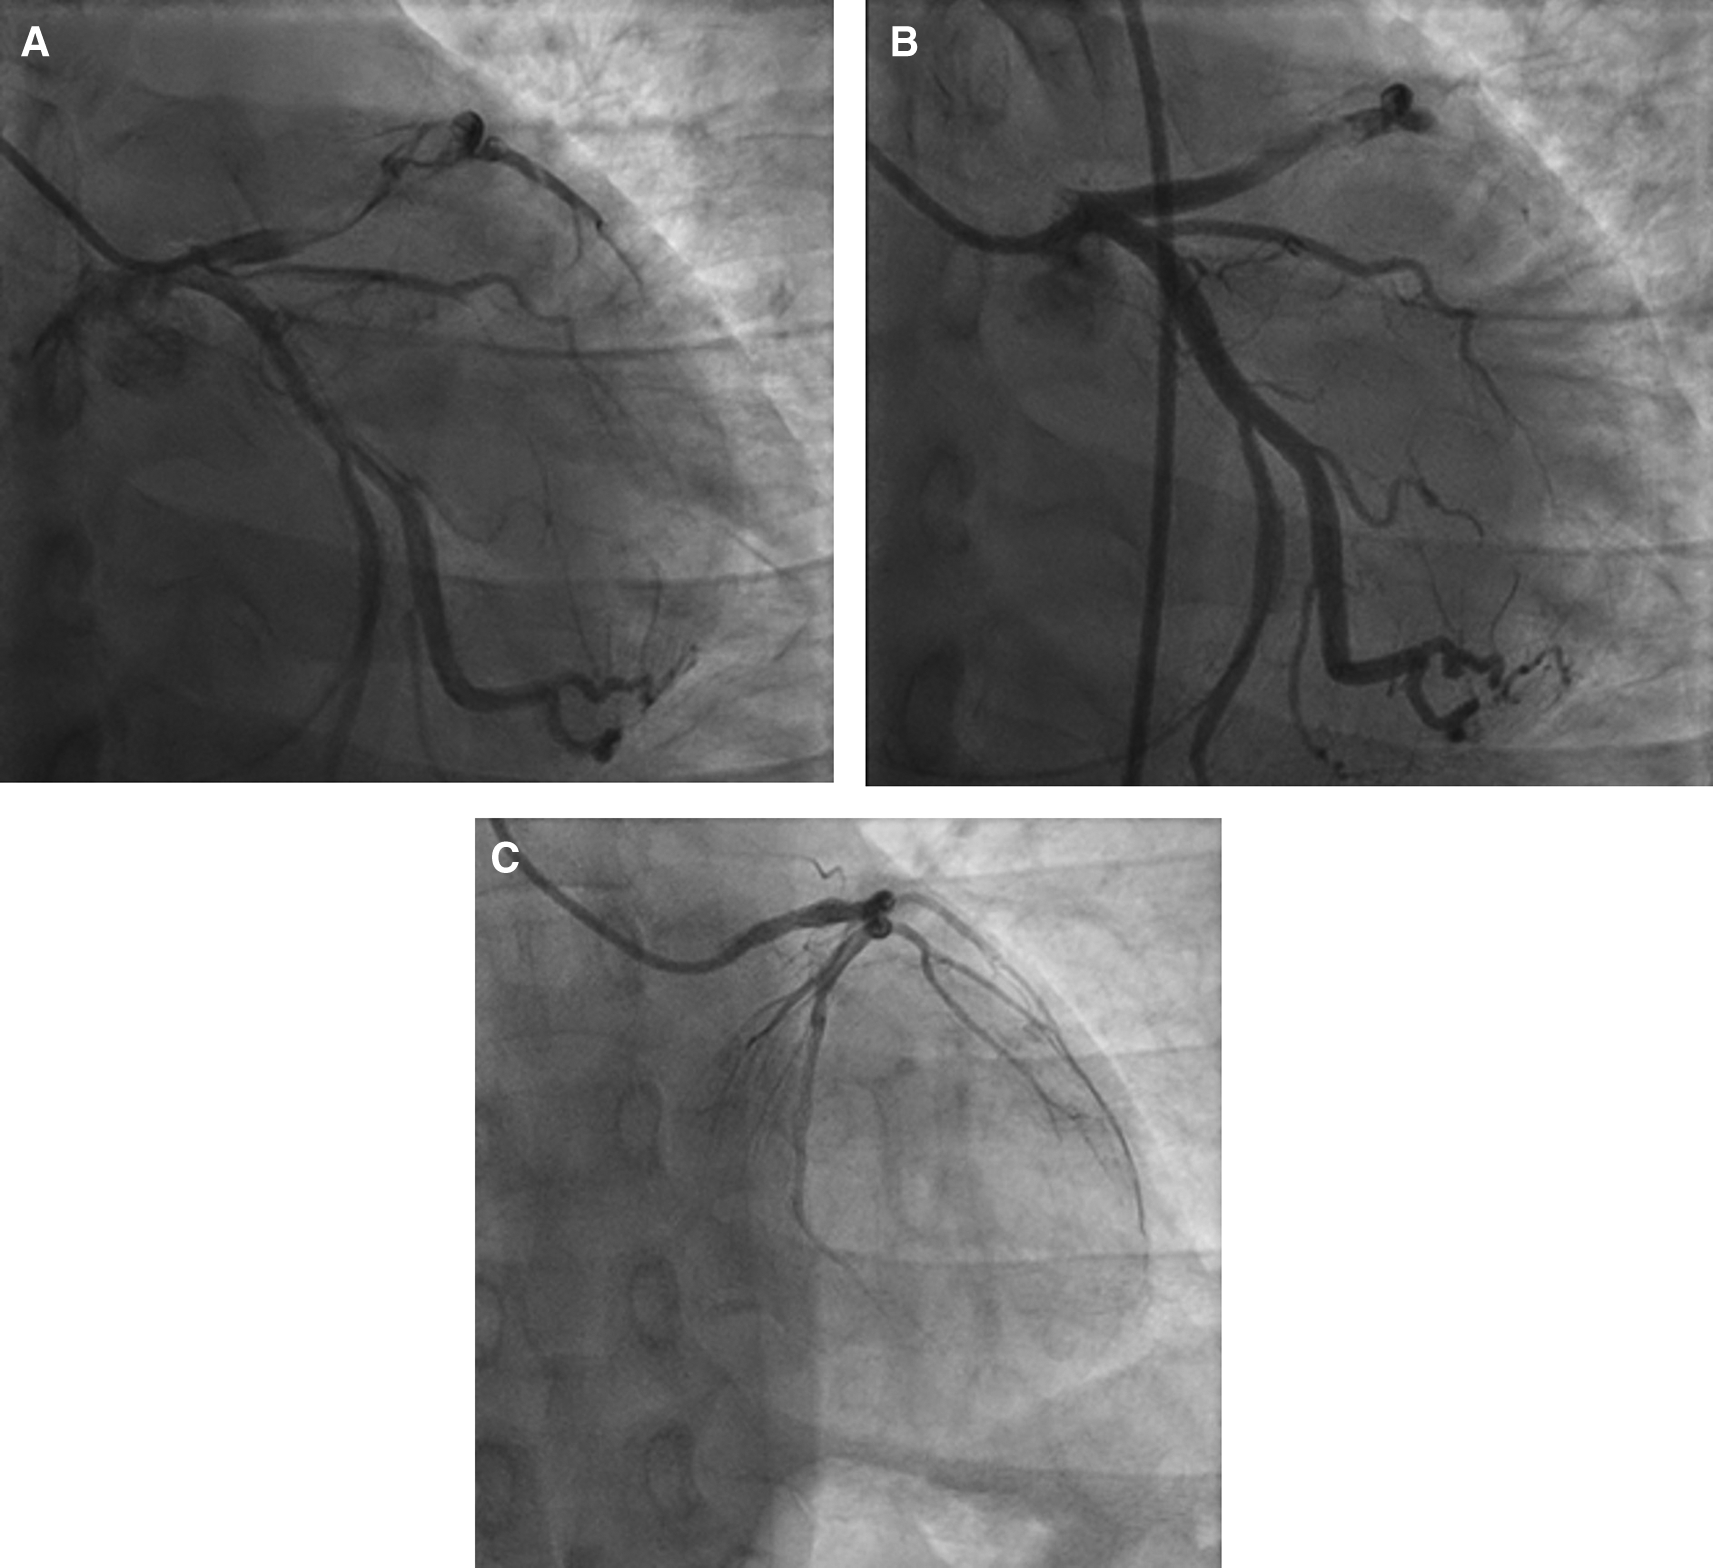

The patient was diagnosed with STEMI anterior extensive, Killip I, TIMI 3/14, nephrotic syndrome, and community-acquired pneumonia. Coroangiography (CAG) revealed total occlusion at proximal left anterior descending (LAD) artery, thrombus grade 5, and TIMI flow 1 (Figure 2A). The patient was then planned to receive plain old balloon angioplasty (POBA) in LAD. After multiple attempts of extensive POBA, CAG showed TIMI flow 1 with residual thrombus in LAD and shifting thrombus to distal left circumflex artery (LCx) (Figure 2B). It was decided to defer further maneuvers and proceeded to medical treatment with intravenous antiplatelet infusion and anticoagulan.

A. Before percutaneous coronary intervention, total occlusion at proximal left anterior descending artery, thrombus grade 5, and TIMI flow 1. B. After percutaneous coronary intervention, TIMI flow 1 with residual thrombus in LAD and shifting thrombus to distal left circumflex artery. C. After 4 months follow-up, normal coronary arteries without any apparent atherosclerotic lesion.

The patient received eptifibatide infusion, heparinization, oral dual antiplatelet with aspirin and ticagrelor, ACE inhibitor, statin, nitrate, and antibiotic. On the following day, there was no chest pain and ECG did not show any dynamic ST-T changes (Figure 1B). The patient was then received steroid therapy and discharged with stable condition. Four months later, without any signs and symptoms, he underwent CAG that showed normal coronary arteries without any apparent atherosclerotic lesions (Figure 2C).